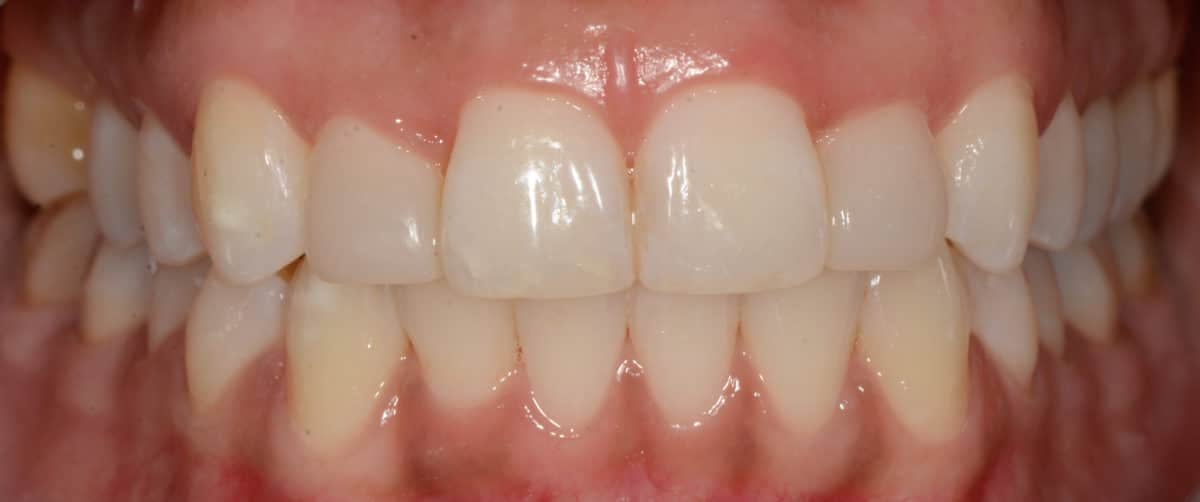

Cas #1 – Traitement avec des bagues, deuxièmes prémolaires et dent de sagesse supérieures ectopiques.